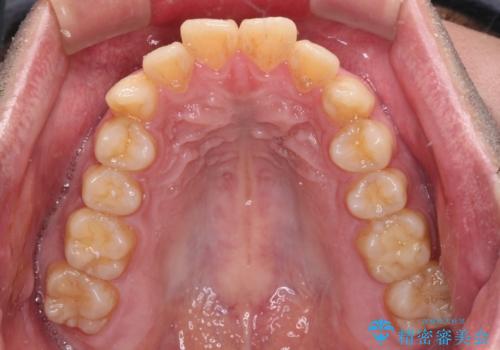

- 前歯のデコボコを治したいとのことで来院された患者様です。

できる限り楽して、短期間で治したいとのことで、ワイヤー装置にて矯正治療を行うこととしました。